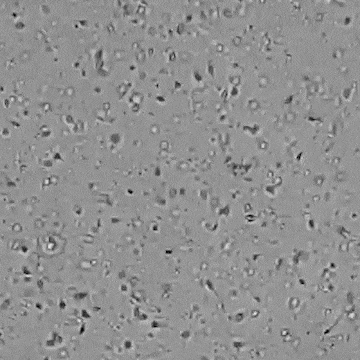

[NEW] 하고보고 정자 관찰기 2세트

집에서 간편하고 신속한 정자 상태 확인!